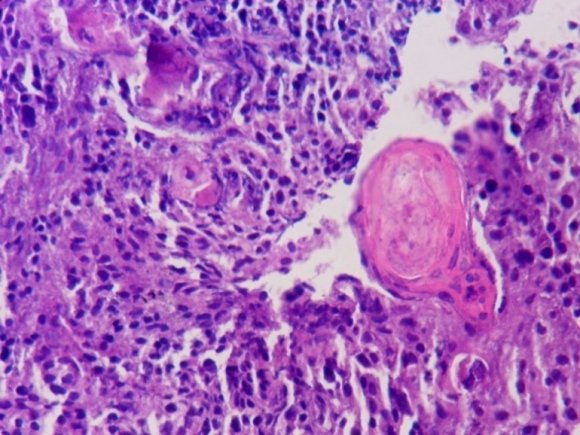

In this study, 59% patients had the cytological diagnosis of benign/ inflammatory and carcinoma was present in 10% of the cases. This is comparable to Saha and Thapa [8] in which benign cases were 51.16% and carcinoma was diagnosed in 6.97% of the cases. Most common cancer in the present study was squamous cell carcinoma (85.18%). This study showed results similar to those seen by Ikram et al [7] (83.33%).

As regards the various histopathological varieties of SCC, the present study found an incidence of 67.39% for moderately differentiated SCC, 23.91% for well differentiated, 8.70% for poorly differentiated. Thus, the findings of the present study are consistent with that

It is concluded that most commonly seen problem, infection, can be controlled with good hygiene. Cervical carcinoma is seen in large number of patients. Pap is a relatively less invasive and a simple procedure to diagnose cervical lesions in developing countries. But sometimes, there can be obscuring of the cellular details by blood, especially in malignant cases. In such cases, biopsy is helpful and confirmatory. of Missaoui et al [6] in that moderately differentiated large